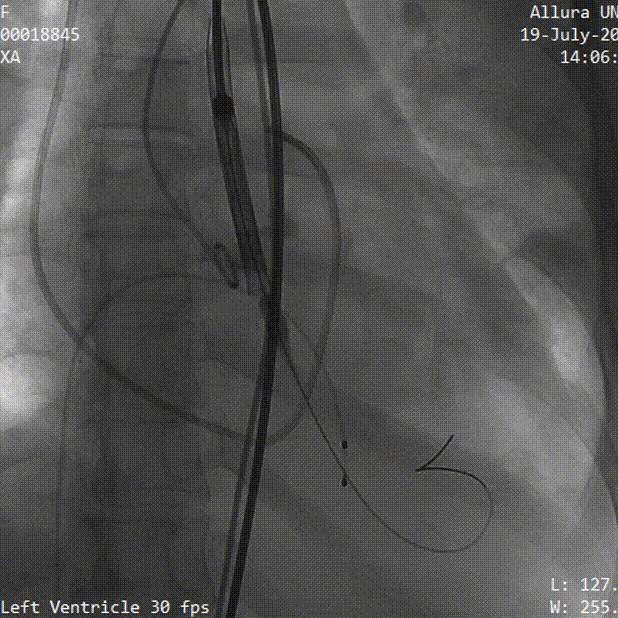

3.TaurusElite AV26号瓣膜定位及释放。瓣膜初始定位瓣下2mm,开花后120次起搏,释放到工作位后造影显示锚定充足,位置良好,冠脉未见遮挡,继续缓慢旋转手柄,瓣膜逐一脱钩,顺利释放。

瓣膜初始定位

瓣膜释放过程

4.释放后多体位观察造影,提示瓣膜位置良好,展开不充分,遂采用20mm及22mm球囊序贯后扩,瓣膜形态明显改善。

20mm球囊后扩

22mm球囊后扩

5.血流动力学监测显示左室充盈压由术前21mmHg降至5mmHg,肺动脉收缩压由68mmHg降至25mmHg,超声提示植入式主动脉瓣活动良好,微量瓣周漏,流速1.52m/s,患者血流动力学改善明显。

6.再次造影检查瓣膜形态良好,无明显瓣周漏,形态良好;造影检查入路血管,无造影剂外渗,手术顺利结束。